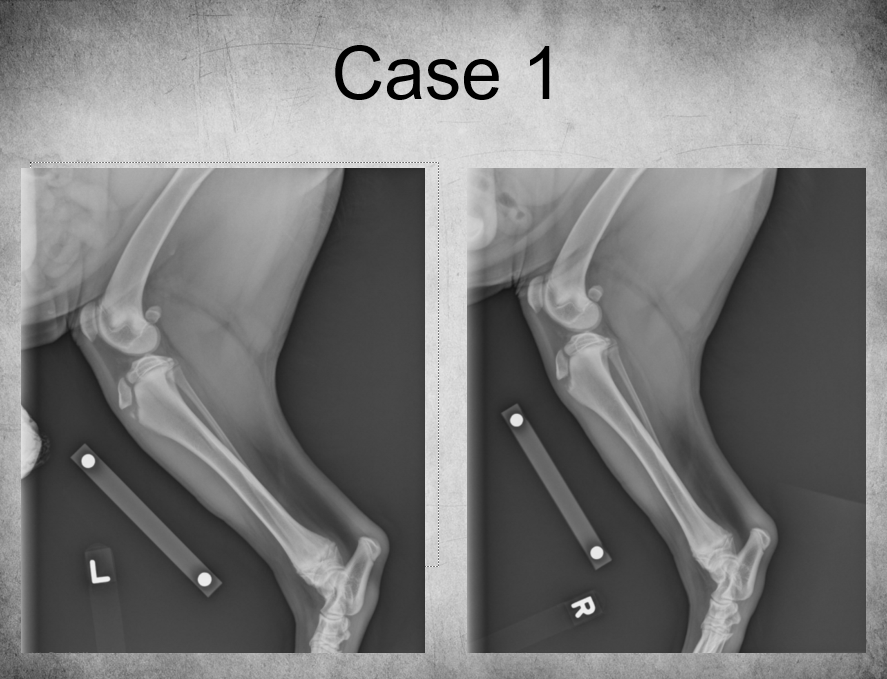

5 months old female Bernese Mountain dog

Played ball with other dogs the previous day

Weight-bearing lameness of left pelvic limb

Mild widening of the left tibial apophyseal physis and small fragment visible at distal portion ->

tibial crest avulsion fracture of growth plate in 5m large breed dog

analgesia and hope it heals okay